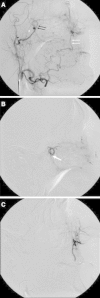

The majority of episodes of spontaneous posterior epistaxis treated with embolisation are idiopathic in nature. The angiographic findings are typically normal. Specific angiographic signs are rare and may include the following: a tumour blush, telangiectasia, aneurysm, and/or extravasation. Selective internal carotid artery (ICA) angiography may show rare causes of epistaxis, such as traumatic or mycotic aneurysms, which require different treatment approaches. Complete bilateral selective external and internal carotid angiograms are essential to evaluation. The images should be analysed for detection of central retinal blush in the external carotid artery (ECA) and anastomoses between the branches of the ECA and ICA. Monocular blindness and stroke are two of the most severe complications. Embolisation aims to decrease flow to the bleeding nasal mucosa while avoiding necrosis of the nasal skin and palate mucosa. Embolisation is routinely performed with a microcatheter positioned in the internal maxillary artery distal to the origin of the meningeal arteries. A guiding catheter should be placed in the proximal portion of the ECA to avoid vasospasm. Embolisation with microparticles is halted when the peripheral branches of the sphenopalatine artery are occluded. The use of coils is not recommended because recurrent epistaxis may occur due to proximal embolization; moreover, the option of repeat distal embolisation is lost. The success rate of embolisation therapy (accounting for late recurrence of bleeding) varies between 71 and 94 %. Results from endoscopic surgery are quite comparable. When epistaxis is refractory to nasal packing or endoscopic surgery, embolisation is the treatment of choice in some centres.